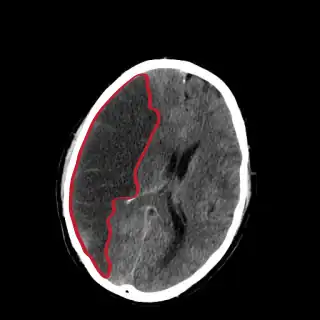

![]() Corte de una TAC del cerebro mostrando un infarto cerebral del hemisferio derecho (lado izquierdo de la imagen). | ||

La tomografía de cráneo revela zonas de infarto mayores de 1,6 cm, pero los cambios de la densidad no son inmediatos, por lo que es un estudio poco sensible. Un error común es realizar una tomografía simple (no contrastada). La inyección de contraste permite realizar una perfu-TC (perfusión por tomografía) y una angio-TC (angiotomografía). El 80 % de las enfermedades cerebrovasculares son debidas a un infarto cerebral isquémico y el otro 20 % a una hemorragia cerebral.[2] Un infarto debe distinguirse de una hemorragia cerebral y de una hemorragia subaracnoidea. Los infartos cerebrales varían en cuanto a gravedad, pues en un tercio de ellos se acaba produciendo la muerte del individuo.